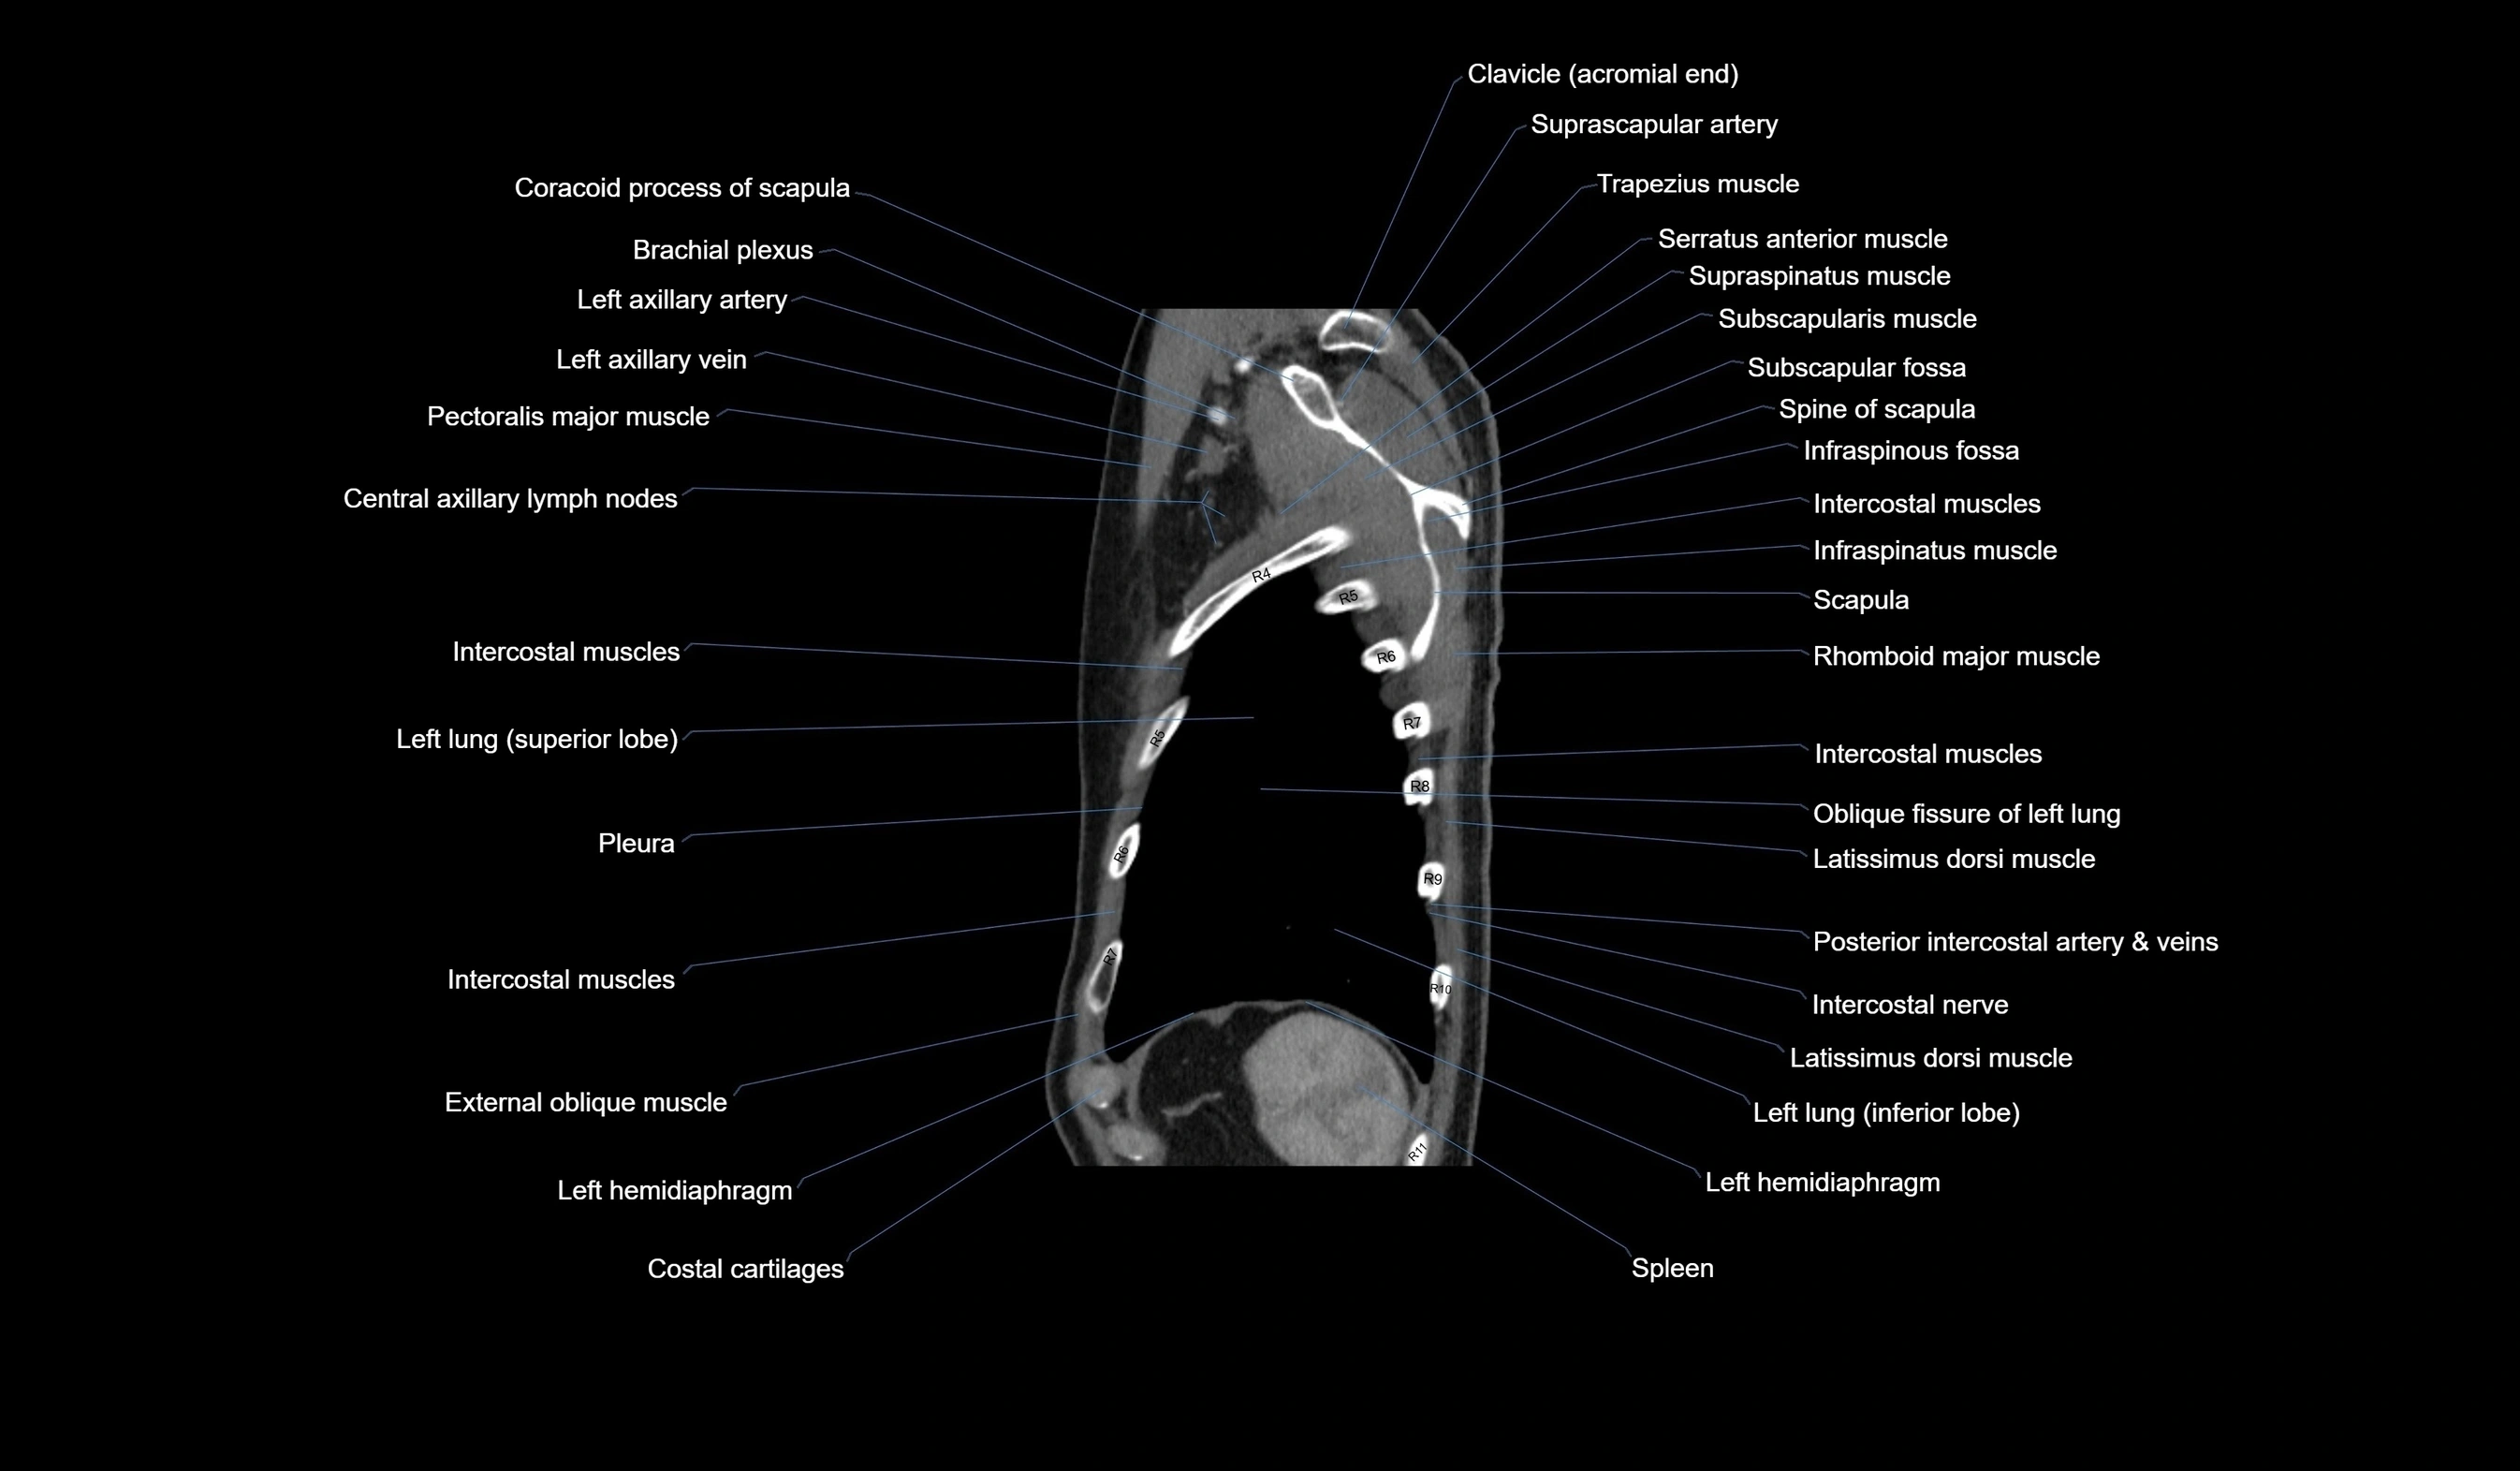

CT images